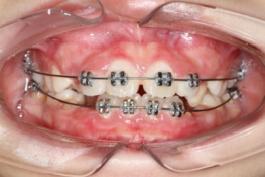

❷ 前牙反牙合:此类错牙合影响下颌前伸,影响上颌发育。

后

❸ 牙齿不齐:影响咬合关系,影响美观。

前